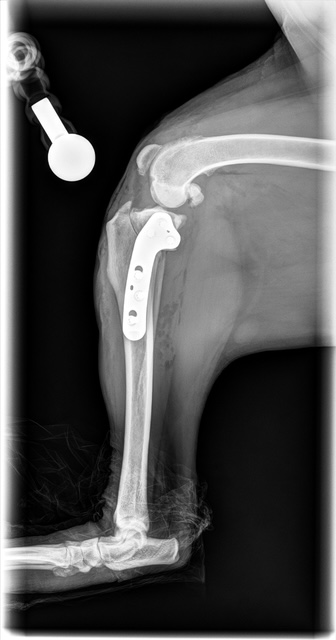

Tibial Plateau Leveling Osteotomy (TPLO)

TPLO is a surgical technique that stabilizes the knee by altering the biomechanics of the joint. By changing the angle of the tibial plateau, the procedure eliminates the need for the cranial cruciate ligament during weight bearing, helping to improve comfort and function during movement.